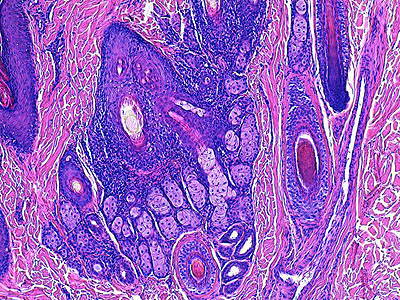

A l’examen histologique, on note une hyperplasie des glandes sébacées qui apparaissent nettement plurilobulées avec un aspect médusoïde très ramifié des lobules d’une même glande, une hyperplasie de la paroi épithéliale des canaux sébacés et de la gaine épithéliale folliculaire externe en région infundibulaire et isthmique ainsi qu’une dilatation kystique des glandes sudorales épitrichiales.

La gaine épithéliale folliculaire externe en zone isthmique et infundibulaire, de même que le canal sébacé, apparaissent hyperkératosiques (orthokératose)(Photos 3,4,5,6). Le pourtour isthmique des annexes est le siège d’un infiltrat inflammatoire lympho-plasmocytaire avec des lésions plus discrètes focales de folliculite murale lymphocytaire (Photos 6, 7). Le reste du derme n’est pas inflammatoire.

Photo 3 : (Hémalun Eosine X 100) : L’épiderme et les infundibula folliculaires montrent

une hyperkératose orthokératosique discrète à modérée, les canaux sébacés et les glandes sébacées

sont hyperplasiques, les glandes sudorales épitrichiales sont rétentionnelles et kystiques.

Légendes de la Photo 3 :

- Pointe de flèche rouge = hyperkératose orthokératosique de l’épiderme

- Étoile turquoise = derme périannexiel non inflammatoire hormis en zone péri-isthmique

- Étoile rouge = glandes sébacées plurilobulées hyperplasiques

- Carré rouge = portions infundibulaires et isthmiques des follicules pileux : la gaine épithéliale folliculaire externe est hyperplasique

- Étoile noire = lumière kystique des glandes sudorales épitrichiales